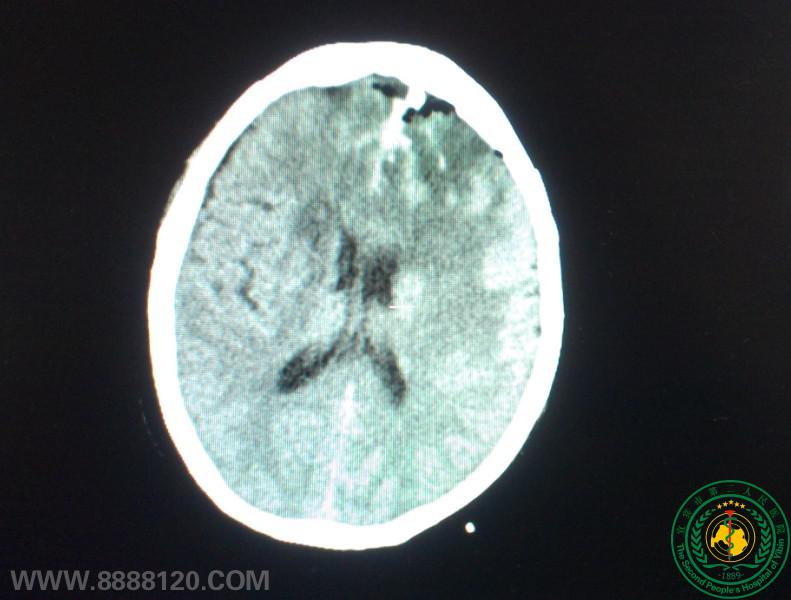

我科顺利完成颅内巨大脑膜瘤一例

我科顺利完成颅内巨大脑膜瘤一例5849